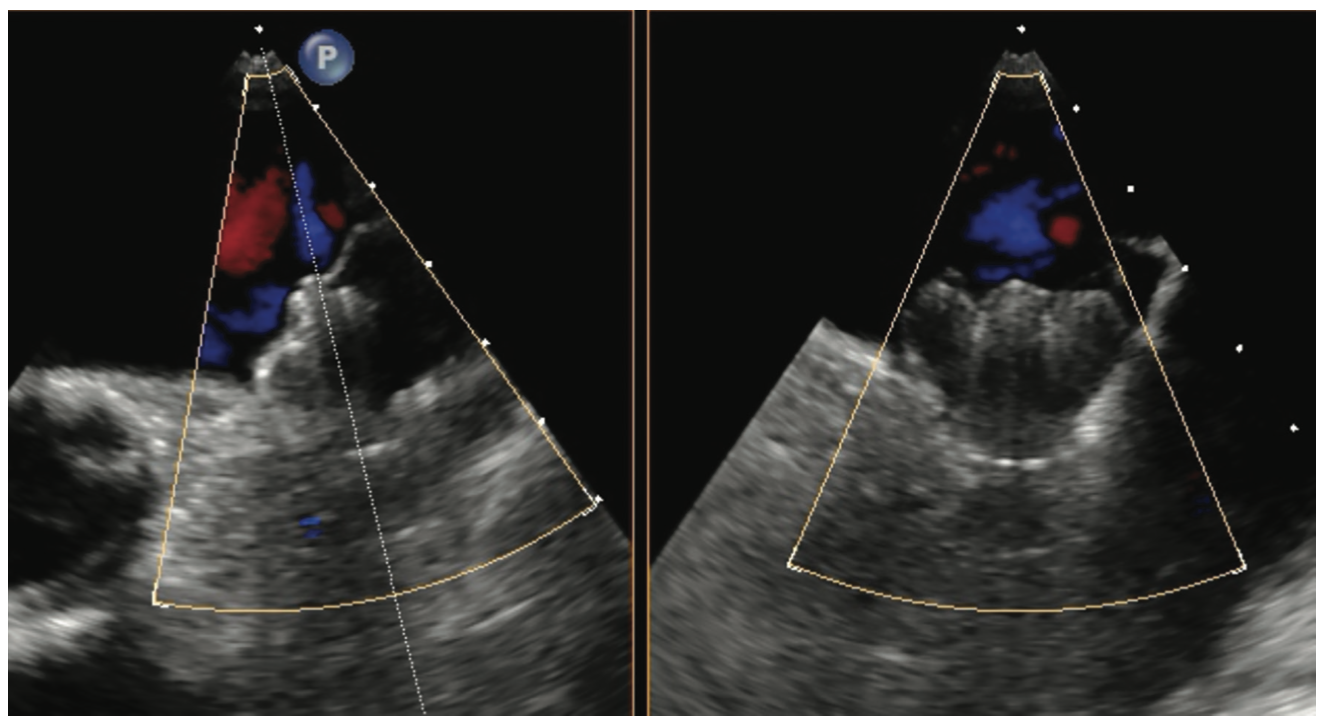

Using TEE 45 days after implantation, we use the same practices, specific angles for evaluation, and x-plane as in the preimplantation TEE (Figures 2 and 3). We also use a reduced viewing angle to only look at one-half of the device at a time, thus increasing the frame rate. Nyquist limits are reduced to be more sensitive to the lower pressures generated in the LA. The study is read immediately and relayed to the implanting physician. Patients are usually seen in the clinic that afternoon and their anticoagulation regimen is adjusted as needed. Video 1 demonstrates a well-seated Watchman FLX device, and Video 2 shows a well-seated Amulet device.